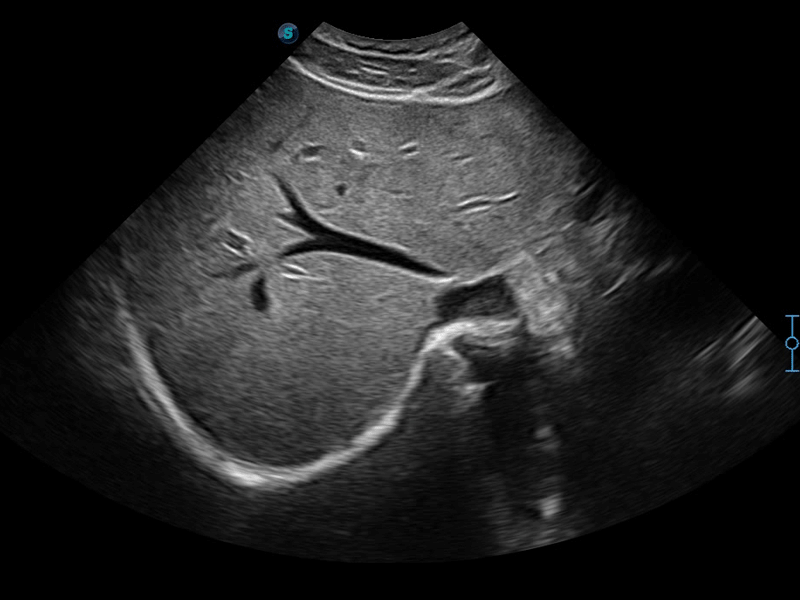

临床图像